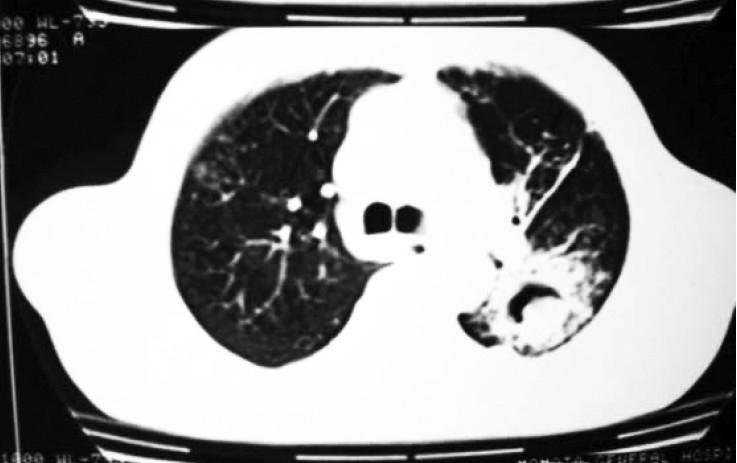

Pulmonary candidiasis presenting as mycetoma.

Candida is a saprophytic yeast that is frequently recovered from the respiratory tract. Most mycetoma lesions are due to Aspergillus species growing inside an existing cavity. The saprophytic nature of the Candida species in the human respiratory tract obscures diagnosis of Candida pulmonary infections. Only a few cases of mycetoma due to Can-dida have been reported. We report a case of mycetoma caused by Candida albicans in a diabetic immunocompromised tuberculous patient. Diagnosis was confirmed by biopsy and certain points strongly favoured the diagnosis. The patient was immunocompromised due to uncontrolled diabetes mellitus. Candida albicans was grown from bronchial and repeatedly from sputum samples and Candida antigen was positive from blood in high titre. There was a good clinical as well as radiological response to antifungal therapy and Candida antigen became negative. We emphasize that in the immunosuppressed host, a mycetoma-like lesion may be caused by Candida pulmonary infection.